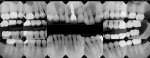

Full-mouth rehabilitation of the worn dentition presents the clinician with many challenges and potential pitfalls. A systematic approach to diagnosis, treatment planning, and risk management is crucial for a predictable outcome. A staged approach to restoring the worn dentition provides the clinician opportunity to evaluate how a patient will respond to occlusal and esthetic changes. In this case, a 61-year-old retired engineer presented with concerns about the wear on his teeth (Figure 1). The case demonstrates the benefits of a staged approach and describes the successful alteration of the initial treatment plan when changes were necessary to better manage risk.

Biomechanical: Caries risk assessment was evaluated using a self-reported questionnaire for risk factors, an adenosine triphosphate (ATP) bioluminescence test, radiographs, and a clinical examination.1 The patient had no cavities within the past 3 years, and no carious lesions were currently present. The ATP bioluminescence test was low (less than 1,500 RLU). His caries risk assessment was determined to be low. Defective restorations were present on teeth Nos. 14, 18, and 31. Many questionable restorations were noted, including the fixed partial denture (FPD) Nos. 7 through 9 (Figure 2). All molars were structurally compromised. While the caries risk was low, the patient’s overall biomechanical risk was increased due to the number of restored teeth, structurally compromised teeth, and failing restorations.

Functional: Since the patient had areas of severe wear that he desired to have restored and an actively changing occlusion, a proper functional diagnosis was imperative. The patient denied any muscle soreness or temporomandibular joint (TMJ) symptoms. His maximum opening was within normal limits at 46 mm, and there was no deviation on opening. Joint load and immobilization tests were negative. A cephalometric radiograph and analysis showed a Class I skeletal relationship. Severe attrition (> 2 mm) was present on teeth Nos. 6, 11, and 22 through 27 (Figure 3 and Figure 4). It is important to note that the lower incisors, despite being worn nearly to the gingiva, contacted the opposing teeth in maximum intercuspal position (MIP). This indicated that the compensatory eruption of the teeth was keeping pace with the rate of wear.

The patient was appointed for postoperative photographs and radiographs (Figure 10 through Figure 13). For added protection, a hard acrylic splint was fabricated for the patient to wear while sleeping.